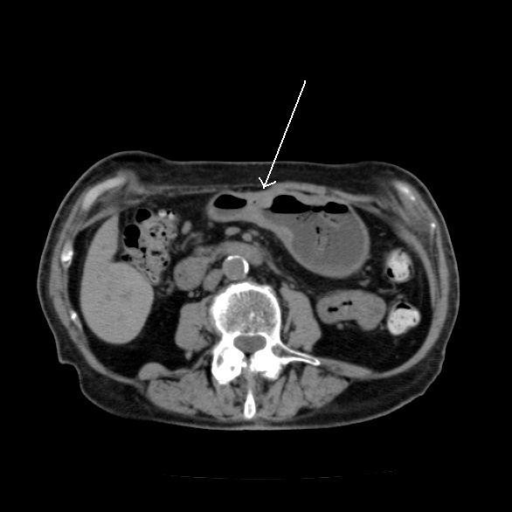

Stomach cancer ct scan images. The stage of your stomach cancer helps your doctor decide which treatments may be best for you. A ct scan uses x rays to make detailed cross sectional images of your body. Imaging tests may be used to help diagnose and stage stomach cancer.

This test is used after a stomach cancer is diagnosed in order to determine the st. Determining the extent stage of gastroesophageal or stomach cancer. Unlike a regular x ray a ct scan creates detailed images of the soft tissues in the body.

If your doctor suspects that you have cancer near your abdomen they may recommend an abdomen ct scan. Ct scans use radiation x rays to form images while colonoscopy uses a flexible instrument equipped with a light and camera to form images. Ct scan images provide more detailed information than plain x rays do.

Ct scans are taken to reveal detailed images of your abdomen. Mri may help doctors stage stomach cancer. A ct computed tomography scan also called a cat scan is a type of specialized x raythe scan can show cross sectional images of a specific area of the body.

The difference between an mri and ct scan. A computed tomography ct scan can give your doctor detailed pictures of structures inside of the body using x rays.